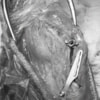

写真の膝関節の垂直線を綿棒の木柄が表しており、遠位の脛骨粗面との位置関係が平行ではありません。

転移側の骨床は犬種特有の変形した表面であったため、転移後の骨片の圧着状態が改善するように変形表面をラウンドバーにて切削しました。滑車溝の著しい低形成が認められたため、滑車溝形成術を実施いたしました。

切断された関節包の縫縮を行いました。前十字靭帯断裂後の不安定性と内旋を解消するために、人工靭帯(fiber wire)によるラテラルスーチャー法を併用し安定化を図りました。